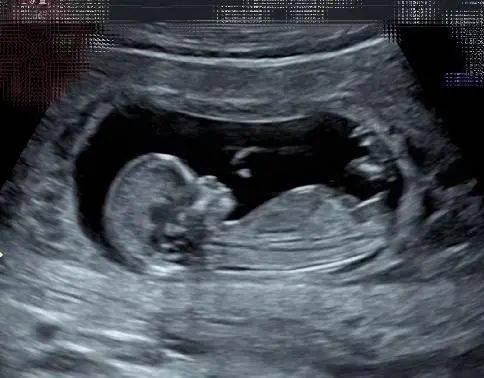

2、b超是很多人都会采用的一种孕检手段,能够检查出胎儿发育基本的情况,这是很重要的,当然,在胎儿不同的发育时期可以看出胎儿不同的发育状况,那么, 50天b超单看胎儿性别准吗 一起来了解一下吧50天b超单看胎儿性别准吗 差不多的1看孕囊看怀孕4050天时的B超单,观察孕囊的大小和形状。

3、许多医生在无特殊情况的情况下,通常不会透露胎儿的性别当孕妇渴望得知宝宝的性别时,可以尝试通过分析B超单来预测那么,如何通过B超单辨别胎儿性别呢B超单上的一些特征能够暗示宝宝的性别以下是两个主要的观察点1 测量数据对比B超单上的长和宽,如果两者差值超过一倍,那么男宝宝的可能性较。

6、很多想知道胎儿性别的准父母会到处打听各种怎么看生男生女的方法,最近我听说了一个b超数据看性别的方法,如何从b超单上辨别胎儿性别呢?b超检查有什么用处对胎儿有影响吗?如何从b超单上辨别胎儿性别 民间说法认为,可以通过以下方法来通过B超数据判断胎儿性别1看孕囊看怀孕第4050天左右检查的。

7、很多准妈妈对于b超的信任度还不够高,或许是因为看不懂b超单数据,而对于b超准不准存在疑惑其实只需要根据网上网友的经验或者按照医生的指导,可以很容易看懂b超数据单的那么,从b超单看胎儿性别准吗 从b超单看胎儿性别准吗 看孕囊孕囊的形状大小是由孕期时间营养着床位置宫腔大小等多种。

10、二四维彩超单 四维彩超可以检查胎儿的脸部身体和四肢是否畸形,也可以看到外生殖器虽然医生看到性别但不能透露,但彩超图像中可能出现的三行可能是YC,可能是女孩三个亮点可能是男孩的标志三孕囊形状 B超单会描述孕囊的大小,并在截图上展示孕囊的形状如果孕囊形状长条,可能是男孩椭圆形或。